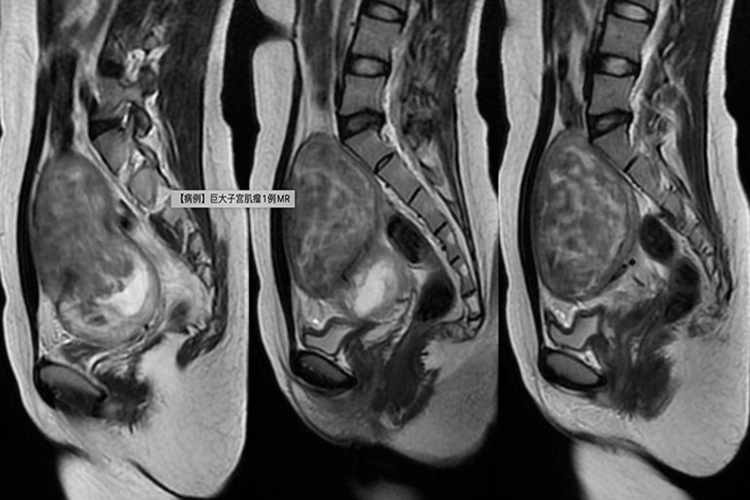

子宫肌瘤

临床表现:子宫肌瘤较小时,多数患者无症状;子宫肌瘤较大时,部分患者有腹痛、月经量大或压迫症状。生长于肌壁间的肌瘤常致月经过多,黏膜下肌瘤常致不规则出血。

影像表现:子宫增大的程度与肌瘤的大小和数目成正比;单发肌瘤多呈低回声结节,边界清,多发肌瘤表现为子宫形态失常,宫壁表面凹凸不平,内多发结节、较大的肌瘤伴后方回声衰减。